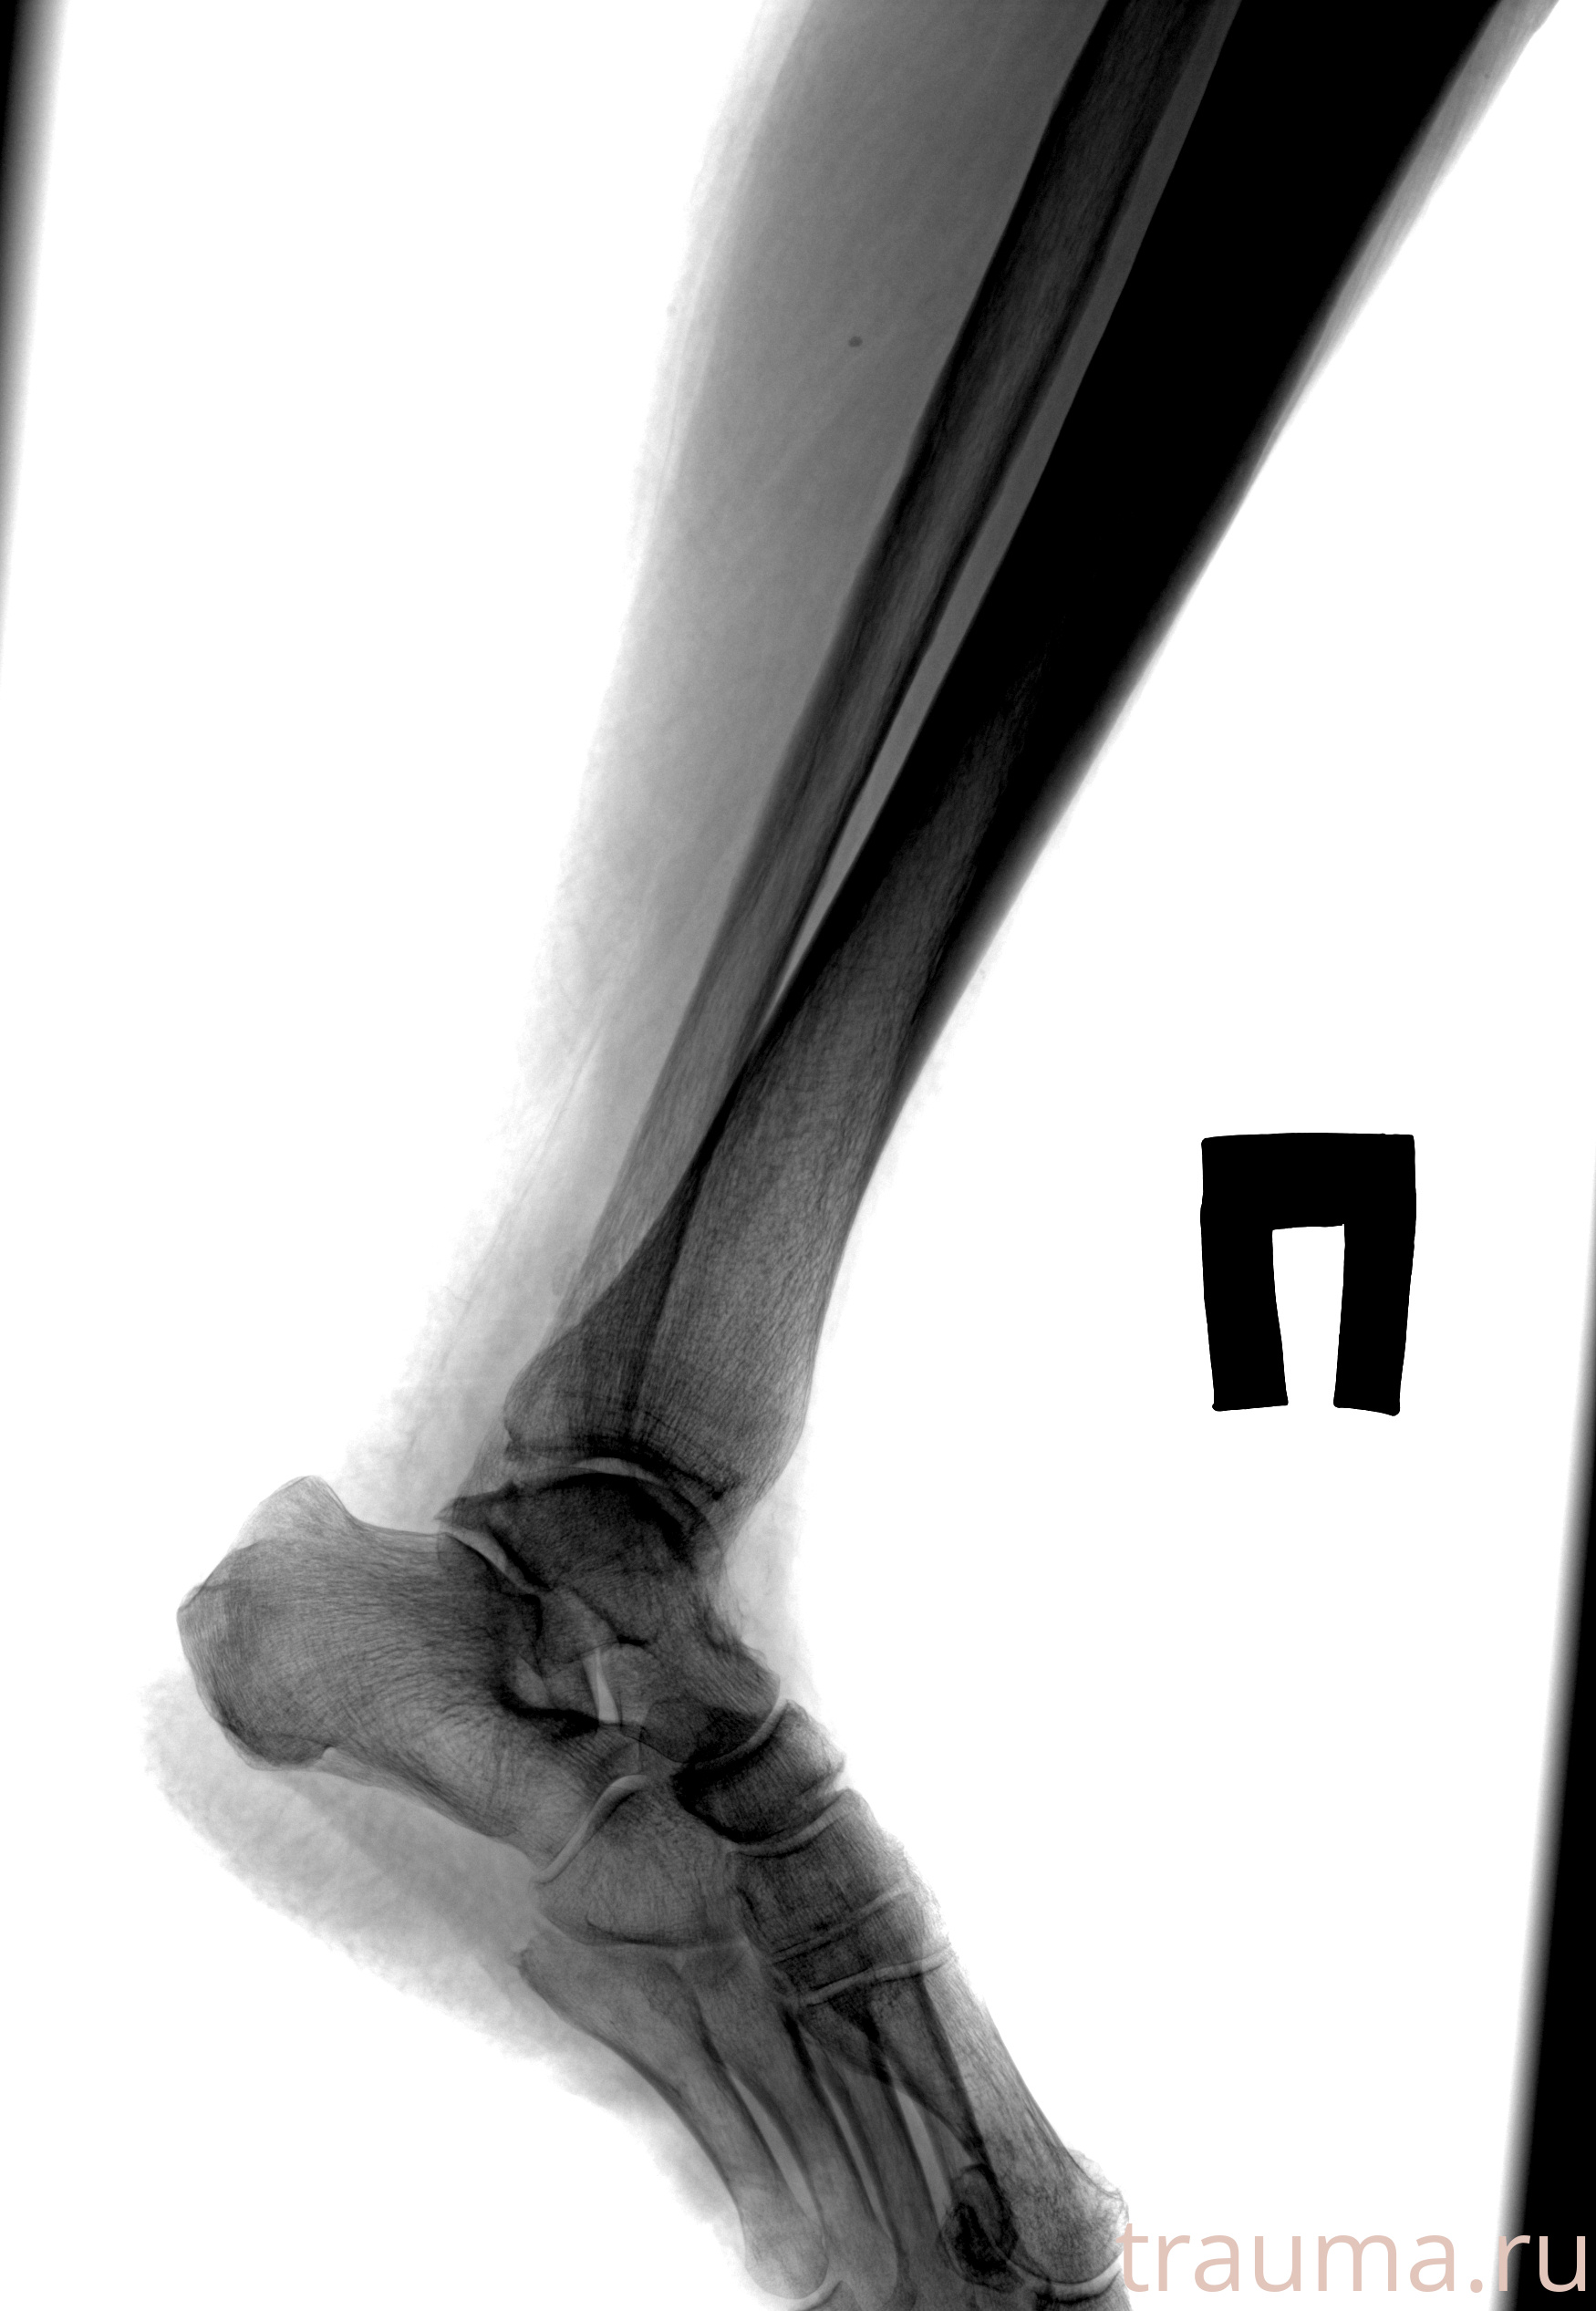

Рентгенограммы

Рентген на дому: по вашему адресу приезжает врач-рентгенолог, травматолог-ортопед с мобильным рентгеновским аппаратом, проводит диагностику травмы или заболевания, делает необходимые рентгенограммы, дает рекомендации по дальнейшему лечению. Получить качественные снимки в домашних условиях возможно благодаря уникальной методике, разработанной МосРентген Центром для института  Склифосовского